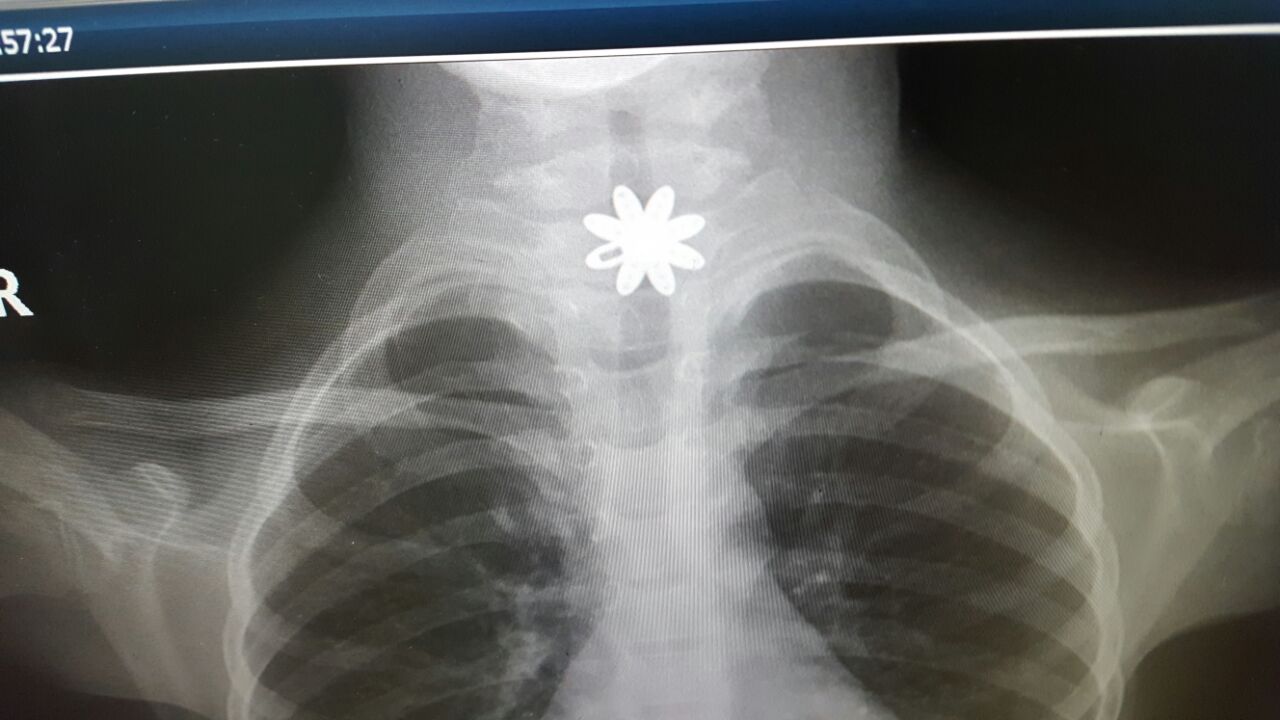

نجح فريقٌ طبي، بمجمع الملك فيصل بالطائف، في استخراج قطعة من الذهب من مريء طفلة تبلغ من العمر سبع سنوات.

كانت الطفلة قد أُدخِلت المستشفى وهي تعاني انسدادًا في المريء، وبعد تشخيص الحالة، اتّضح وجود قطعة معدنية حادة تشكِّل خطورةً على حياة الطفلة، ممّا أدّى إلى جروحٍ قطعية داخل المريء.

وخضعت الطفلة لعملية، باستخدام منظار المريء الصلب، لاستخراج القطعة المعدنية، في وقتٍ قياسي وبشكلٍ دقيقٍ وسريع، وتمّت معالجة الحالة، حيث غادرت المستشفى بصحةٍ جيدة.